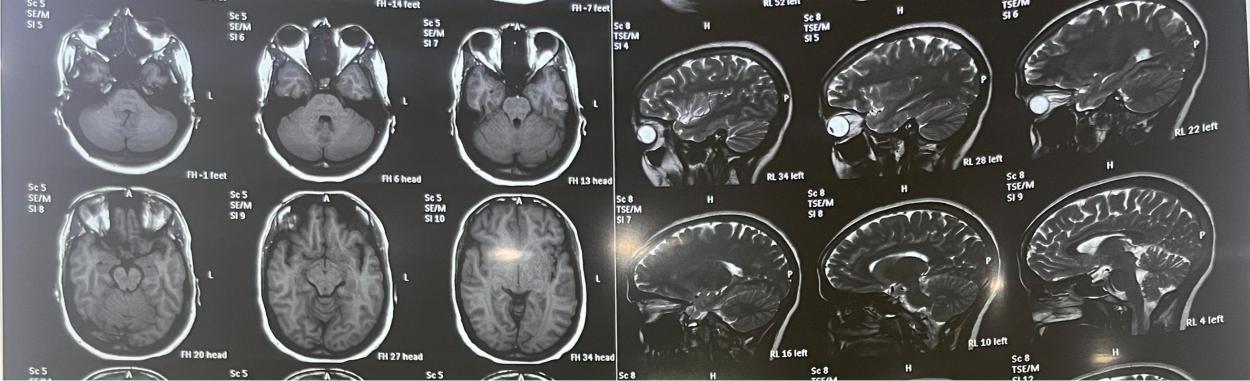

CASE 2

A 30 y old female presented with a complaint of severe throbbing headaches in both temporal regions for two months. The headache had been exacerbated for one month and was accompanied by nausea, vomiting, and retroorbital pain. The patient's headache is bad enough to wake her up from sleep. Complaint of blurred eyesight for one month, which was temporary. The patient also has a complaint of diplopia. Upon testing, she was discovered to be overweight, having a BMI of 24.5. An eye examination revealed abducens nerve palsy. During an opthalmoscopic examination, the right eye showed slight blurring of the disc edge as well as mild venous tortuosity. In the left eye, there is 360 °C blurring of the disc edge. There was more papilloedema in the left eye than in the right. The lumbar puncture was performed under high opening pressure of 230 mmH2O. The CSF count, sugar, and protein levels were all within normal limits. A blood test revealed dyslipidemia, which is defined by elevated cholesterol and triglycerides. An MRI brain with orbit was performed, which revealed that the orbital section of the optic nerve is tortuous and kinked bilaterally. Flattening of the posterior sclera and protrusion of the optic nerve head on both sides, as well as large CSF sleeves around the optic nerve, suggest pseudotumour cerebri fig. 2. The patient was originally treated with acetazolamide 500 mg BD and mannitol (20%) TID. We also administered dexona 8 mg TID injections for three days, followed by oral steroids in tapering doses. The patient was encouraged to lose weight and change her lifestyle. After discharge, oral acetazolamide was continued. After 15 d, a follow-up revealed minimal papilloedema with significant reduction in symptoms. patient came for second follow up after 3 mo with no symptoms and examination revealed no Papilloedema.

Fig. 2: MRI brain with changes of IIH